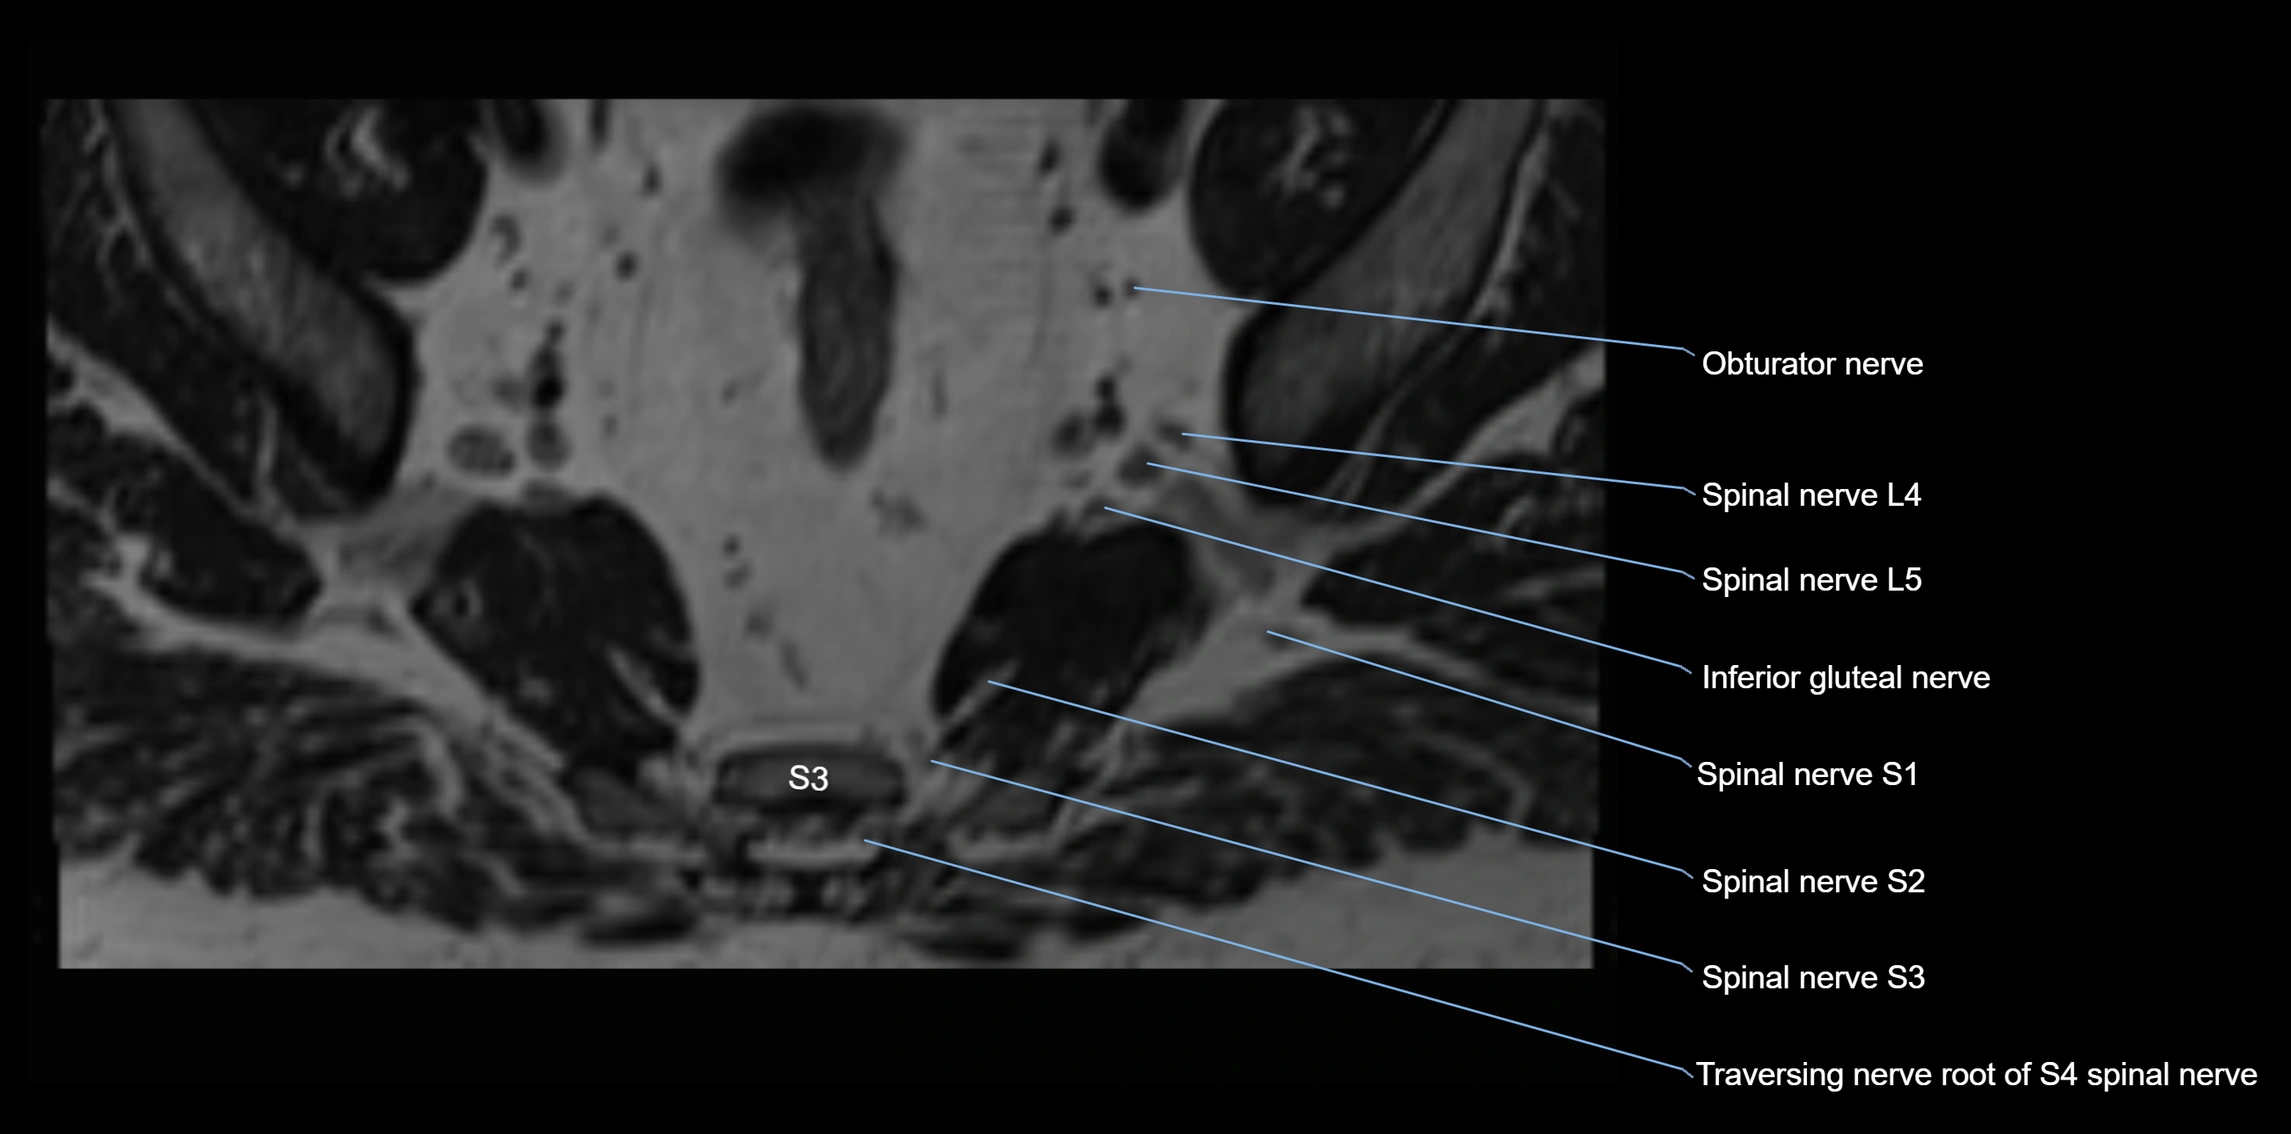

MRI Appearance

T1-weighted images:

• Nerve appears as a very thin low-to-intermediate signal intensity structure

• Surrounded by bright fat, aiding visualization

T2-weighted images:

• Nerve shows intermediate to mildly hyperintense signal compared to muscle

• Pathological involvement appears brighter

STIR (Short Tau Inversion Recovery):

• Normal nerve appears dark

• Inflamed or entrapped nerve appears bright hyperintense

T1 Fat-Sat Post-Contrast:

• Normal nerve enhances minimally

• Pathologic nerve (neuritis, entrapment, tumor infiltration) shows focal or diffuse enhancement

3D T2 SPACE / CISS:

• Nerve appears intermediate to mildly hyperintense compared to muscle

• Surrounded by bright fat or CSF, improving visualization

• Best sequence for mapping small pelvic nerves such as the anococcygeal